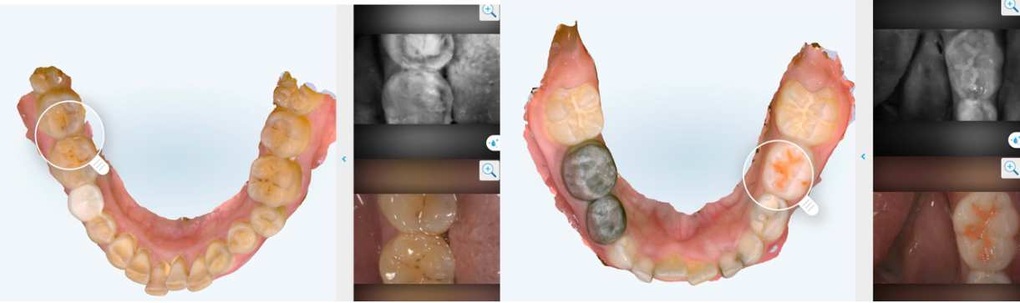

Hình ảnh sâu răng mặt bên R75 được phát hiện tại Nha khoa Như Ngọc bằng ánh sáng cận hồng ngoại của máy quét trong miệng iTero Lumina Pro (Ảnh: Nha khoa Như Ngọc).

Hình ảnh sâu răng mặt bên ở răng 84 và 85 dưới ánh sáng cận hồng ngoại của máy quét iTero 5D Plus (Ảnh: Nha khoa Như Ngọc).